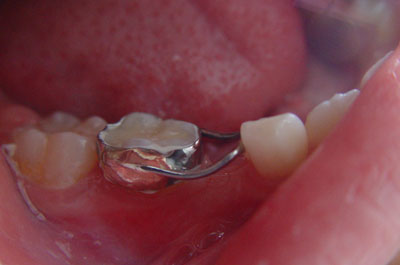

(1)缺隙保持器

2、固定矫治器 它粘固在牙齿上,可以精确地移动牙齿,能够矫治各种复杂的错合畸形,矫治效果好,是目前国内外最常使用的矫治器。各种固定矫治器大都由带环、矫治弓丝、托槽等三部分组成。我国自从开展固定正畸以来,先后用过Begg细丝弓矫治器、方丝弓矫治器、直丝弓矫治器来矫治错合畸形。目前国内普遍采用的是直丝弓矫治器。按照直丝弓托槽的槽沟角度的不同设计,常用的直丝弓矫治器又可分为Roth系列直丝弓矫治器、OPA-K直丝弓矫治器、MBT直丝弓矫治器等。按照托槽所用材质的不同,可以分为国产金属托槽、进口金属托槽、生物陶瓷托槽。